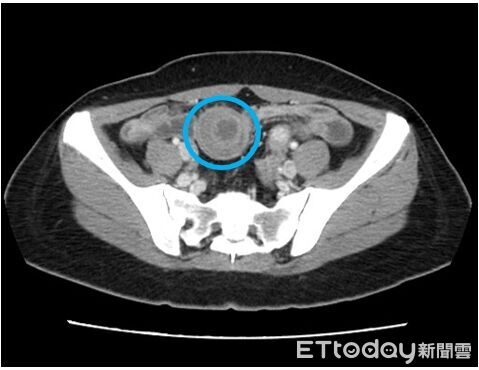

ETtoday

一位45歲的王姓女子一個多月以來飽受腹部疼痛與胃痛困擾,經診斷為小腸套疊,套疊得如望遠鏡,卻驚人發現腸套疊的元凶,竟是小腸黏膜下層一顆三公分罕見腫瘤。平等澄清醫院一般外科王志浩醫師表示,腫瘤因其生長位置與特性,常會引發嚴重的腸套疊,若不及時處理,恐引發腸道缺血壞死或穿孔危及生命。